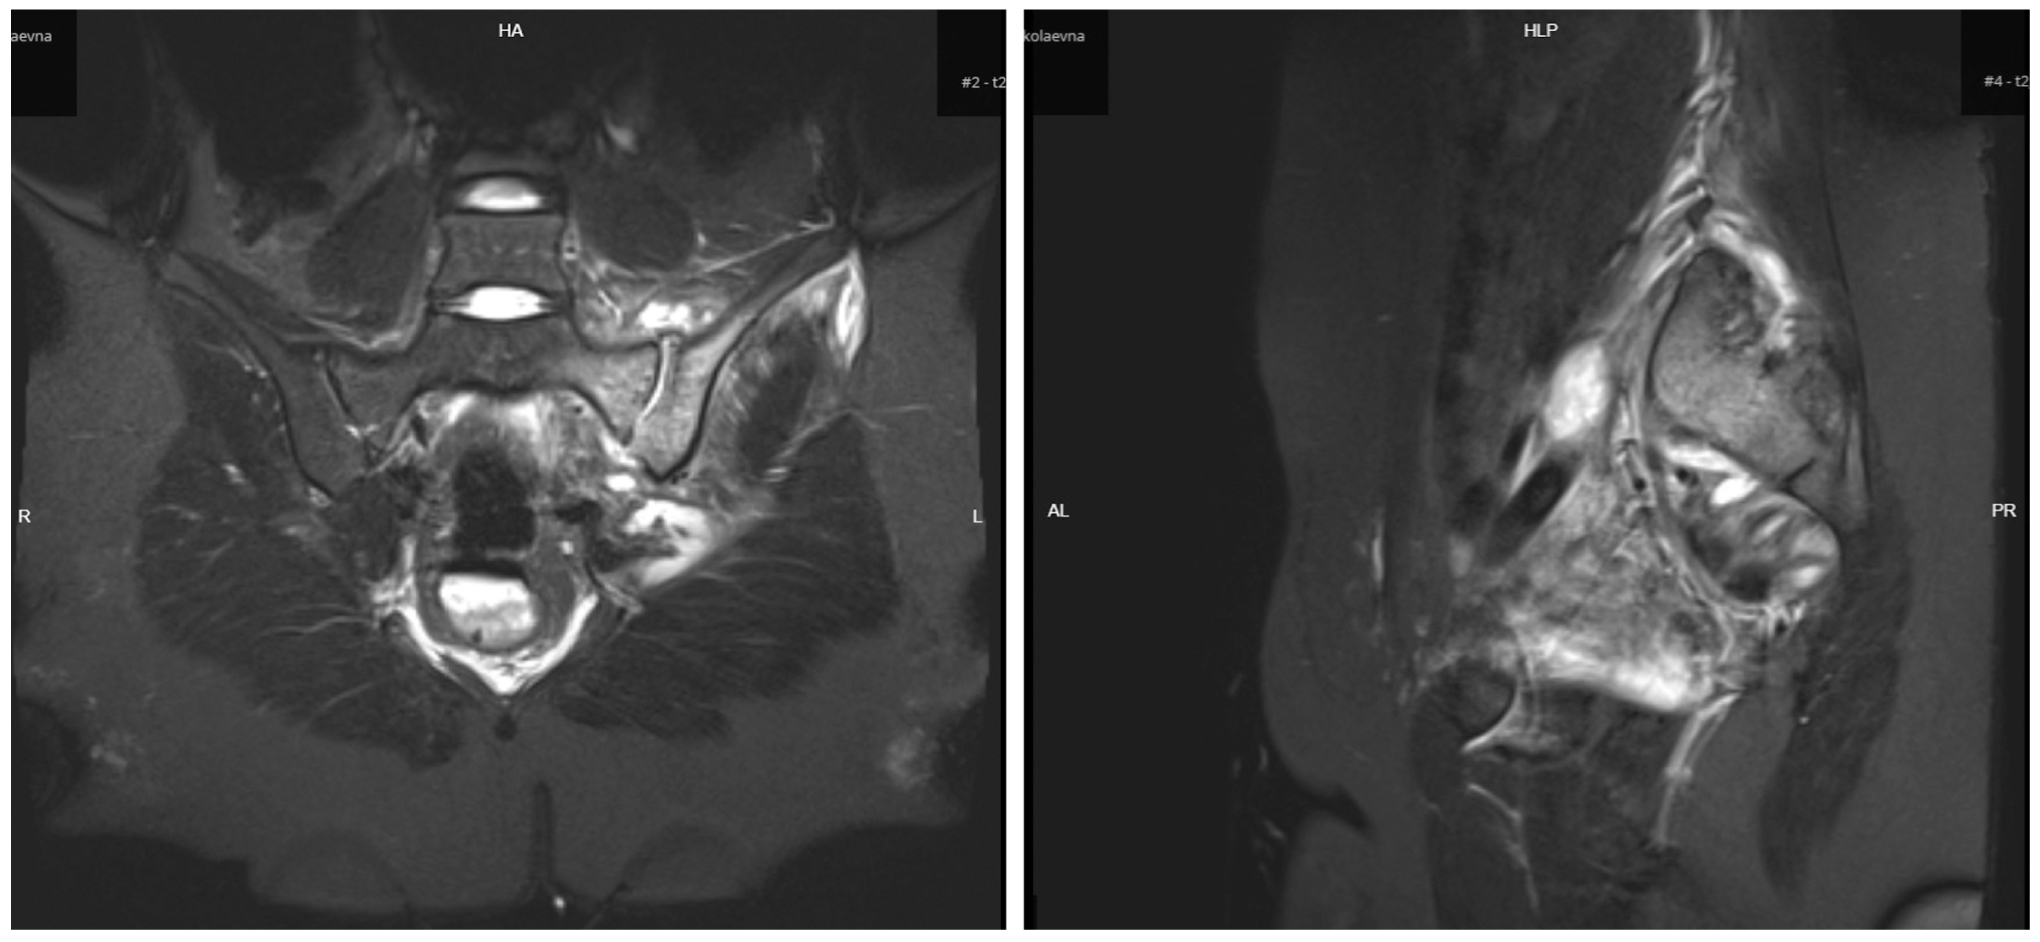

Остеомиелит крестца и копчика может быть как первичным заболеванием, проявляющимся свищами с гнойным отделяемым в крестцово-копчиковой области, так и осложнением любого гнойно-воспалительного процесса. Характерными клиническими проявлениями являются симптомы интоксикации и местная воспалительная реакция. Для заболевания характерно рецидивирующее формирование гнойных свищей. Пальпация крестца и копчика при проведении пальцевого ректального исследования позволяет выявить патологическую подвижность костей, участки размягчения. При зондировании, фистулографии, УЗИ мягких тканей выявляется связь с костными структурами. Наиболее информативным методом является МРТ, при котором помимо достоверной визуализации свищевых ходов можно чётко дифференцировать очаг воспаления в костной ткани (рис. 7).

Рис. 7. Магнитно-резонансная томограмма: остеомиелит крестцовой и подвздошной костей.

Fig. 7. Magnetic resonance imaging: osteomyelitis of the sacral and iliac bones.